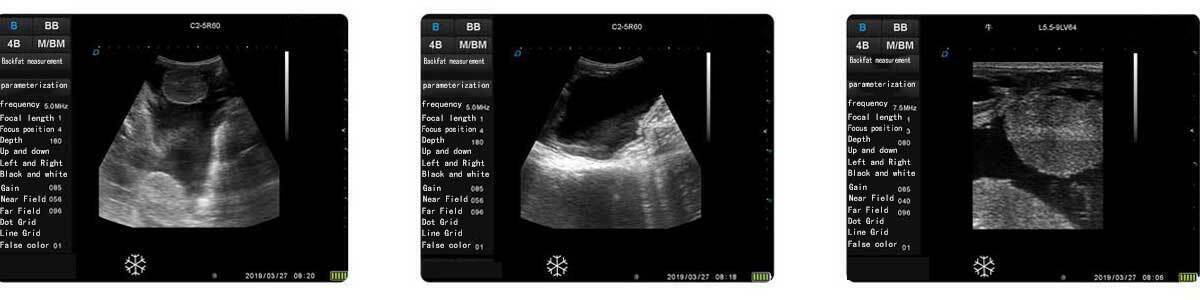

ECO-15Vet Bovine with Wireless Goggles, Convex Rectal Probe

ECO15Vet veterinary ultrasound diagnostic machine is a newest research and development product by Dawei Veterinary Medical (Jiangsu) Co, Ltd. It adopts the new Acorn RISC Machine, compared with the traditional Microcontroller Unit, it has the characteristics of faster processing speed, stronger processing capacity, larger storage capacity, higher security performance, easier upgrade and maintenance, etc., which effectively brings greater convenience to users.

Display mode: B, BB, 4B, BM, M